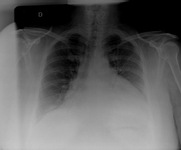

Evaluación del derrame pericárdico

El RT en un paciente con un derrame pericárdico que muestra hallazgos típicos de una silueta cardíaca en forma botella de agua con una raya de grasa pericárdica gruesa y diferenciada.

De la colección del Dr. Rajdeep Khattar